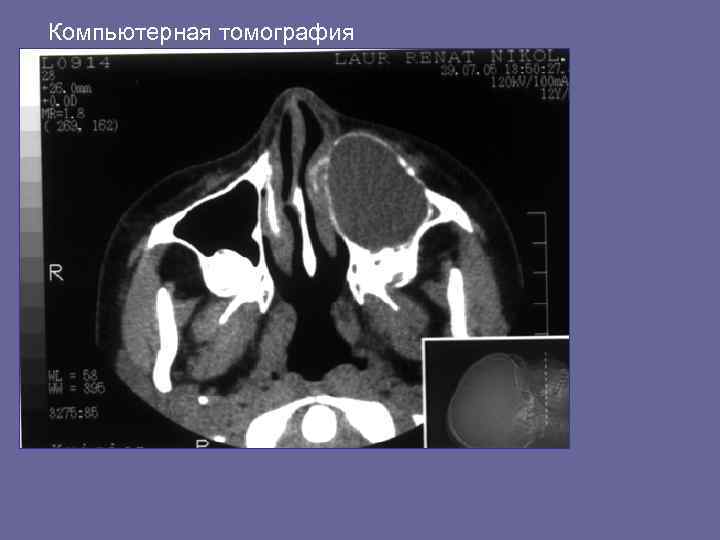

Компьютерная томография